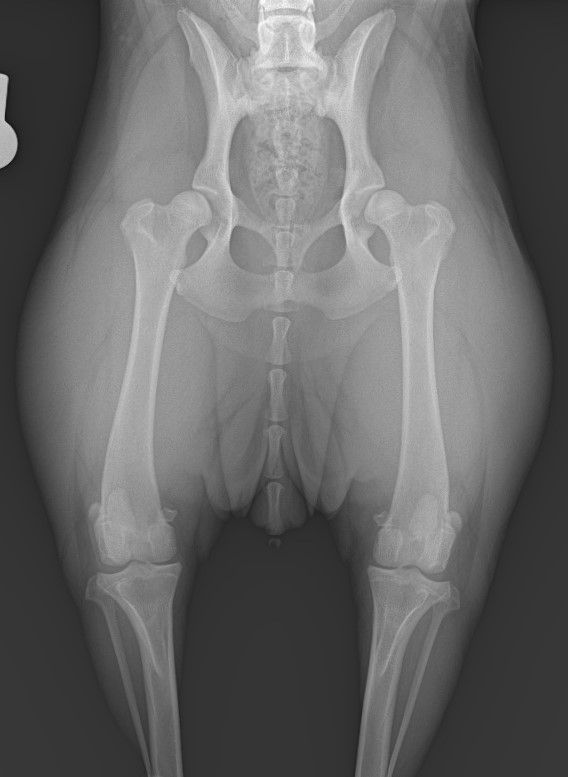

OFAの股関節評価は、1枚の専用レントゲン画像(伸展位) をもとに、寛骨臼の深さ・大腿骨頭の形・関節裂隙などを総合的に判定します。

股関節の評価は、正確なポジショニング がとても重要です。大腿骨の回転が少しでもある、骨盤が左右で傾く、尾の位置がずれるなどで 評価が不正確になることがあります。できるだけ正確な姿勢で撮影することで精度の高い評価を目指しています。